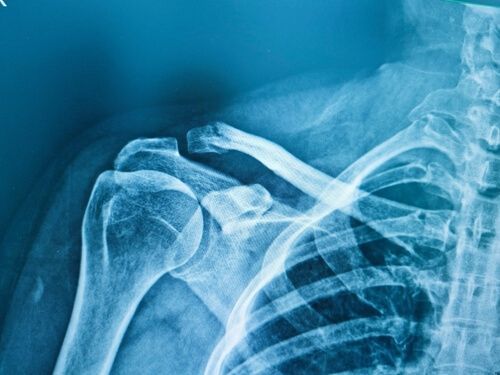

- X-ray – This is the most common imaging test and provides a clear view of the bone structure.

- CT scan – In some cases, a CT scan may be ordered to provide a more detailed image of the fracture.